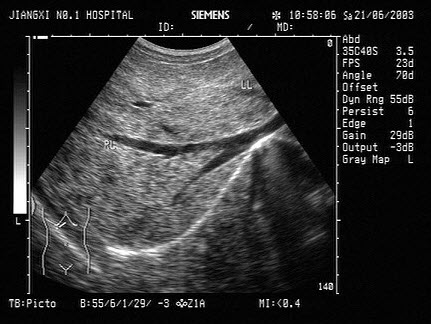

8、单项选择题

患者,女,35岁,有急性胰腺炎病史,现感上腹不适。结合中上腹超声声像图表现,诊断是()

A.胰腺占位并胰管扩张

B.急性胰腺炎

C.慢性胰腺炎并胰管结石

D.胆总管结石

E.胰腺癌